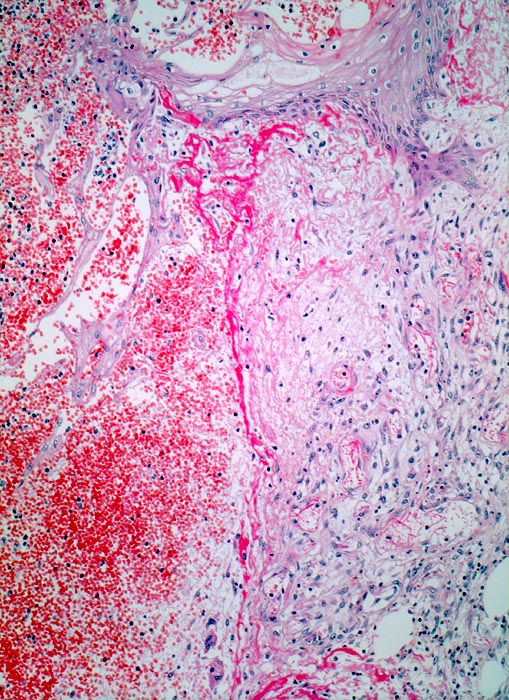

Wundheilung: Granulationsgewebe

Entzündung / Reparatur

Haut, Rumpf

Blutgefüllter spaltförmiger Defekt im Corium. Am Rand der Wunde rechts im Bild ödematöses Granulationsgewebe mit zahlreichen kapillären Gefässen, Fibroblasten und wenig Entzündungszellen. Hellrote Fibrinauflagerungen auf dem Gewebsdefekt. Neugebildete Epidermis überzieht teilweise den Wundgrund.

6 Tage alte Wunde am Abdomen nach Laparotomie.